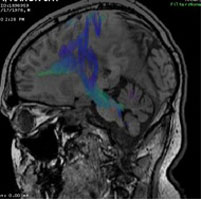

The UAB Department of Radiology at present has eight clinical MRI units, with construction in the University Hospital North Pavilion completed in the past year adding large bore 1.5 and 3T systems. An extremity MRI is conveniently located in the orthopedic clinics at UAB Highlands hospital. All MR machines have the full complement of coils, high performance gradients, and post processing capabilities in place to perform state of the art imaging including advanced diffusion weighted and diffusion tensor imaging, dynamic contrast enhanced and dynamic susceptibility enhanced MRI. Images sent from the Kirklin Clinic or University Hospital MRI suites to the 3D Laboratory for Multimodality Imaging for Patients, the MNIRC (Multidisciplinary NeuroImaging Resource Core) or CCQIBAD (Comprehensive Core for Quantitative Imaging Biomarker Analysis and Development) can be manipulated using TeraRecon, Dynasuite, StealthViz, Neuro IB platforms or study-specific software developed by UAB personnel.

Research MRI examinations are performed on the UAB Radiology Department's clinical magnets as well as on dedicated research units located in the Boshell Building and in the Civitan International Research Center. Advanced post processing of imaging data from all three resources may be additionally performed investigators in the MNIRC, CCQIBAD, or the Laboratory for Multimodality Imaging for Small Animals in the Division of Advanced Medical Imaging.